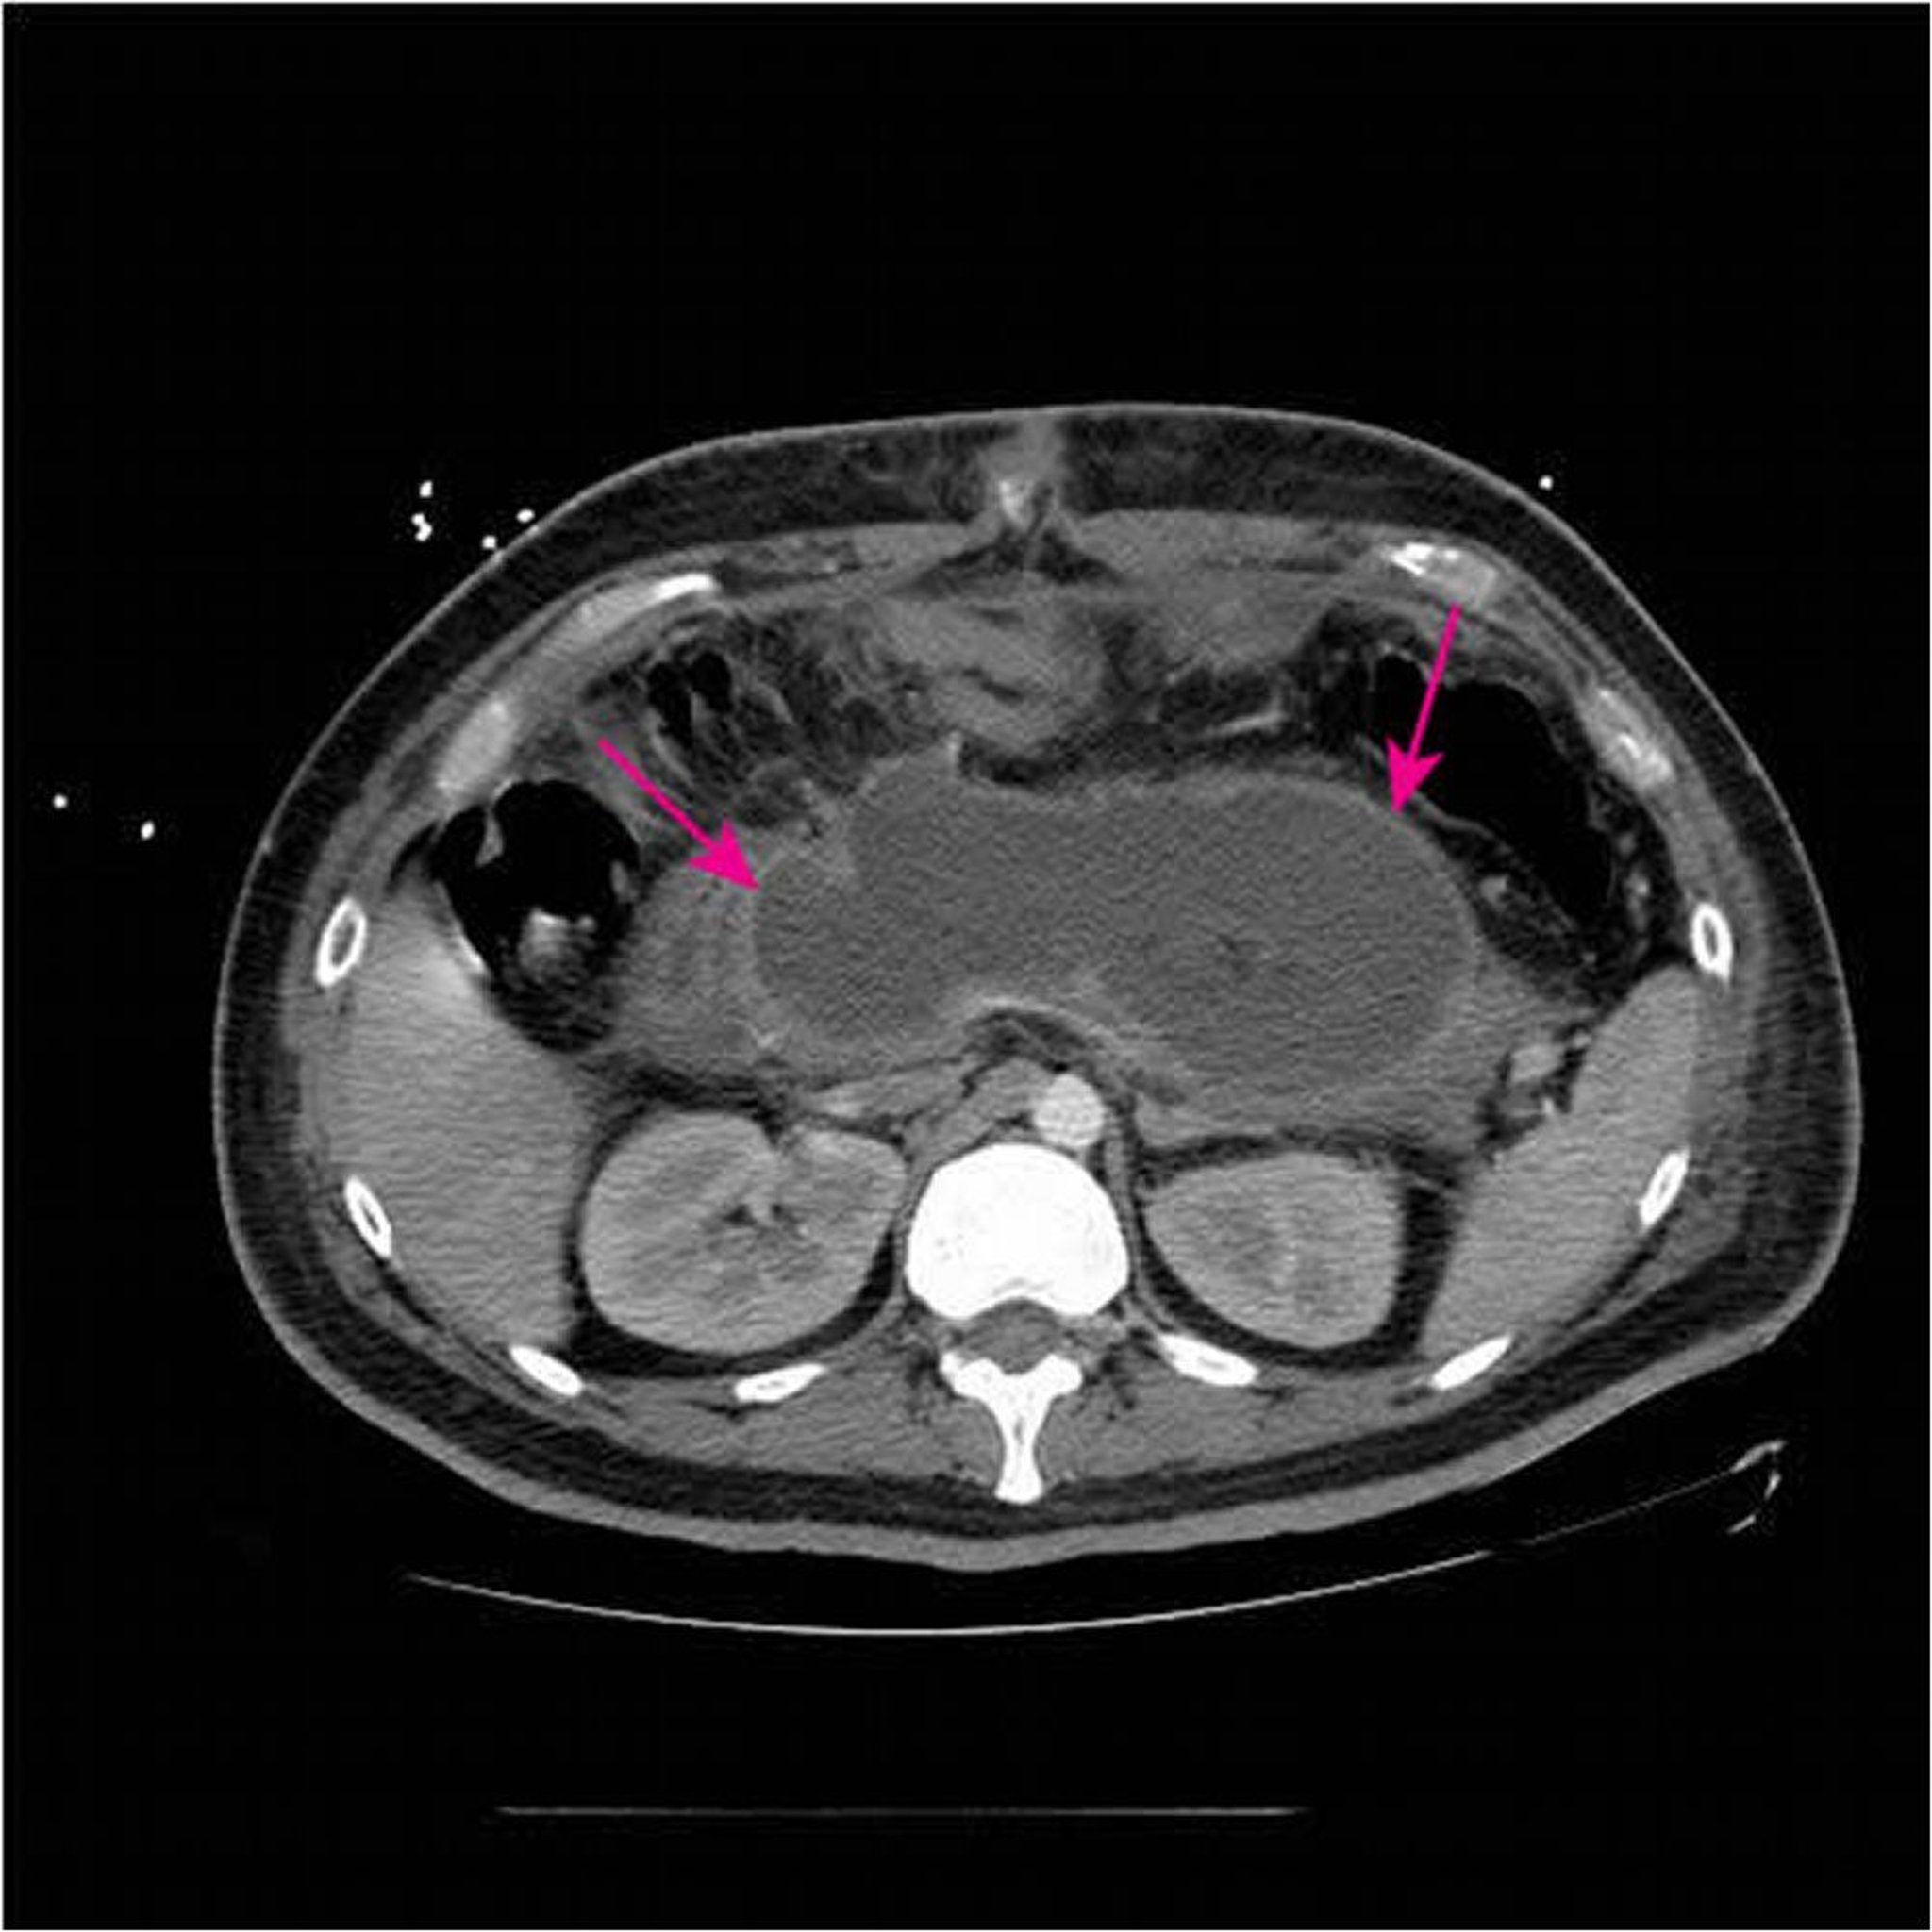

Collection nécrosante aiguë

Cette TDM avec contraste IV et oral montre une grande collection nécrosante aiguë (flèches) remplaçant la majeure partie du tissu pancréatique < 4 semaines après la présentation initiale d'une pancréatite nécrosante.

Image courtesy of Sonam Rosberger, MD.